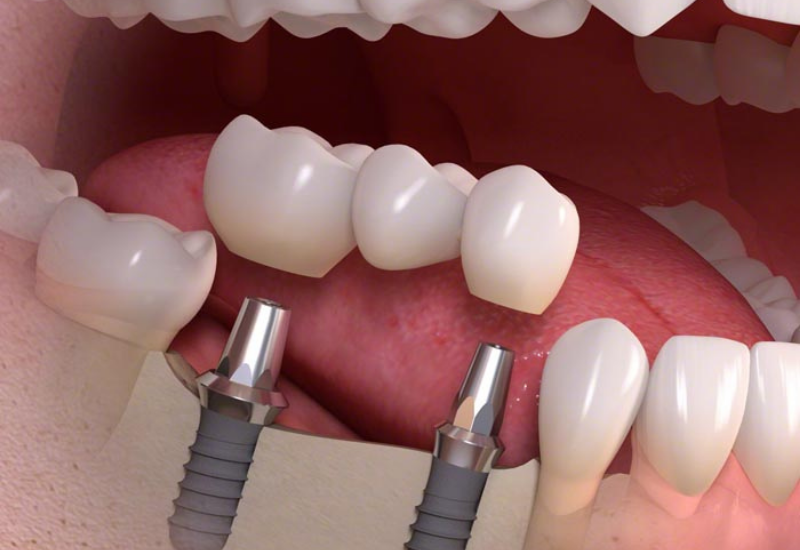

A fogászati híd egyszeres- vagy többszörös foghiányt átívelő fix fogpótlás, mely a maradék fogakon, vagy az azokat helyettesítő implantátumokon oldhatatlanul rögzül. Rendelőnkben a hagyományosan, pillérfogakon rögzített híd mellett természetesen az implantációs fogpótlások is elérhetők.

2.: Az implantációs híd ezzel szemben előzetesen beültetett implantátumokra, azaz műgyökerekre illeszkedik.

2. Az implantációs híd

Az implantációs híd esetén az elhorgonyzást nem a saját fogak, hanem implantátumok biztosítják. A fogimplantátum egy speciális titán csavar, amely az elveszett fog gyökerét pótolja. Az implantátum behelyezése műtéti beavatkozást igényel.

Miután az implantátum becsontosodott (integrálódott) az állcsontba, többhónapos gyógyulási szakasz után történhet meg az implantátumok felszabadítása, majd újabb, pár hetes gyógyulási szakasz után a lenyomatvétel. A híd elkészítésének lépései ezitán már nagyon hasonlóak, mint a fogakon rögzülő híd esetében.

Az implantátumokon elhorgonyzott híd elkészítése lassabb folyamat, hiszen meg kell várni a beültetett fogimplantátum becsontosodását, ami esettől függően körülbelül 4-9 hónapot jelent. Ugyanakkor érdemes kivárni ezt az időt, hiszen jóval tartósabb, terhelhetőbb, esztétikusabb megoldást nyújt, mint egy kivehető fogpótlás.